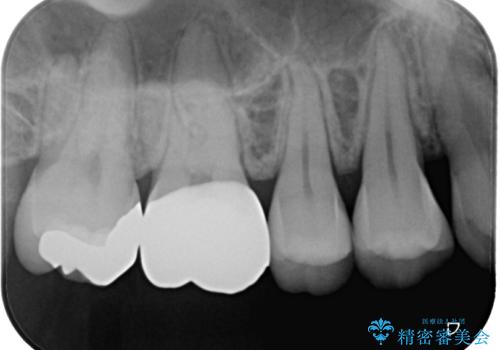

右上の6番目の歯はメタルインレーが大きかったためルジルコニアクラウン、右上の7番目の歯は一番奥で審美的な要素よりも機能面を重視してゴールドインレー修復による治療計画を立案しました。

拡大鏡視野下で保険のプラスチック(コンポジットレジン)、虫歯を除去し、フルジルコニアクラウン、ゴールドインレーに適した形にしました。

歯と歯茎の間に圧排糸と呼ばれる糸を入れてシリコーン印象を行いました。

見た目と機能面ともに満足していただきました。